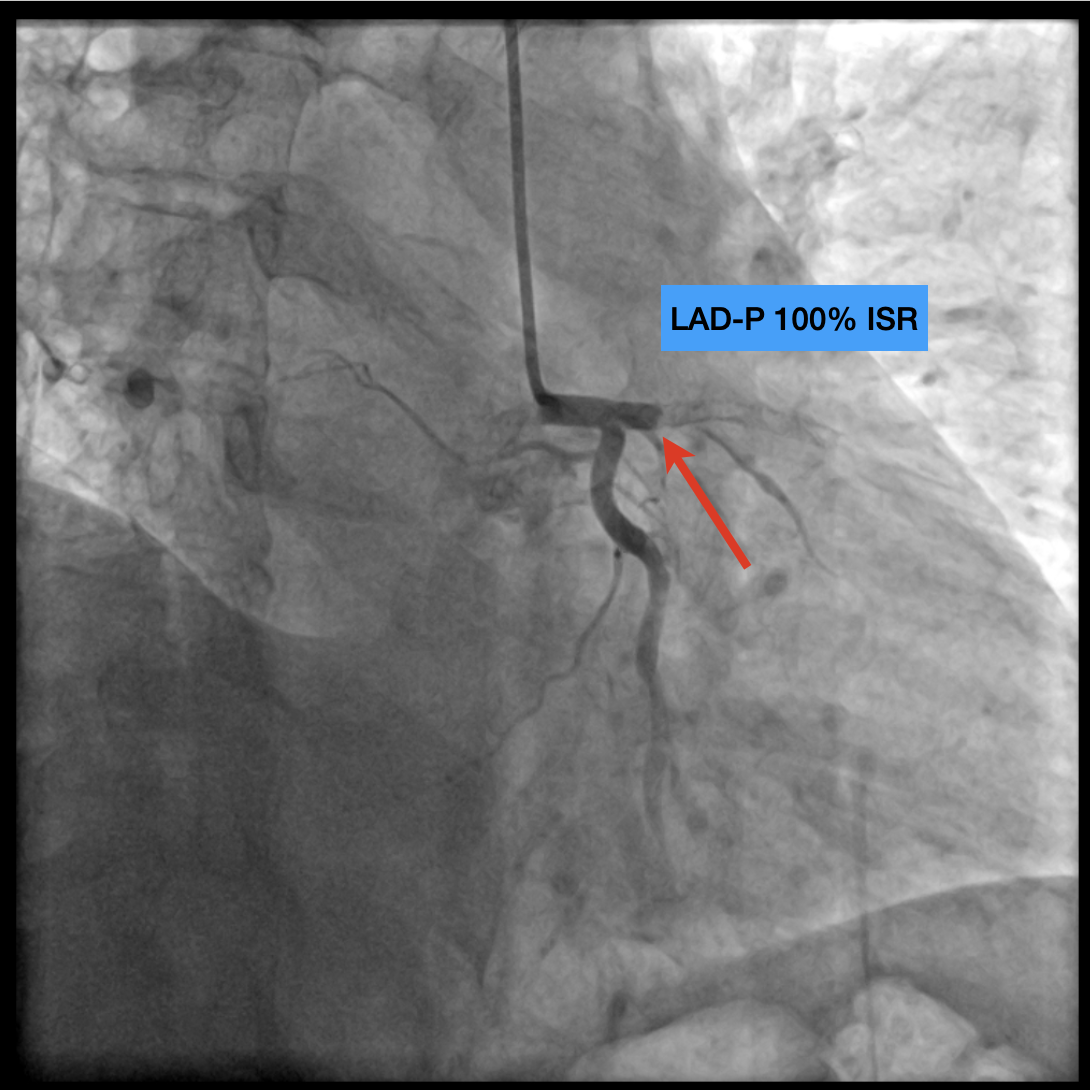

CAG report: CAD with TVD s/p PCI at LAD-P, 100% instent restenosis